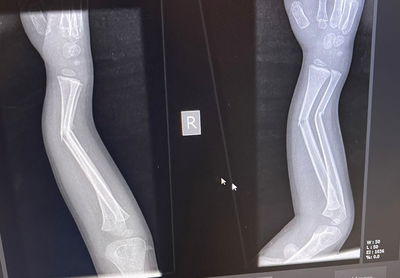

ד"ר דייויד זלוטניק, מנהל רפואי בטרם: "עונת הקיץ בכלל, והחופש הגדול בפרט, מועדים לתאונות רבות של ילדים. ברכיבה על אופנים יש להקפיד על ליווי מבוגר, חבישת קסדה ומתן הנחיות ברורות, במיוחד לילדים קטנים, העלולים לסבול מפציעות חמורות גם בנפילה מגובה נמוך" (בריאות)